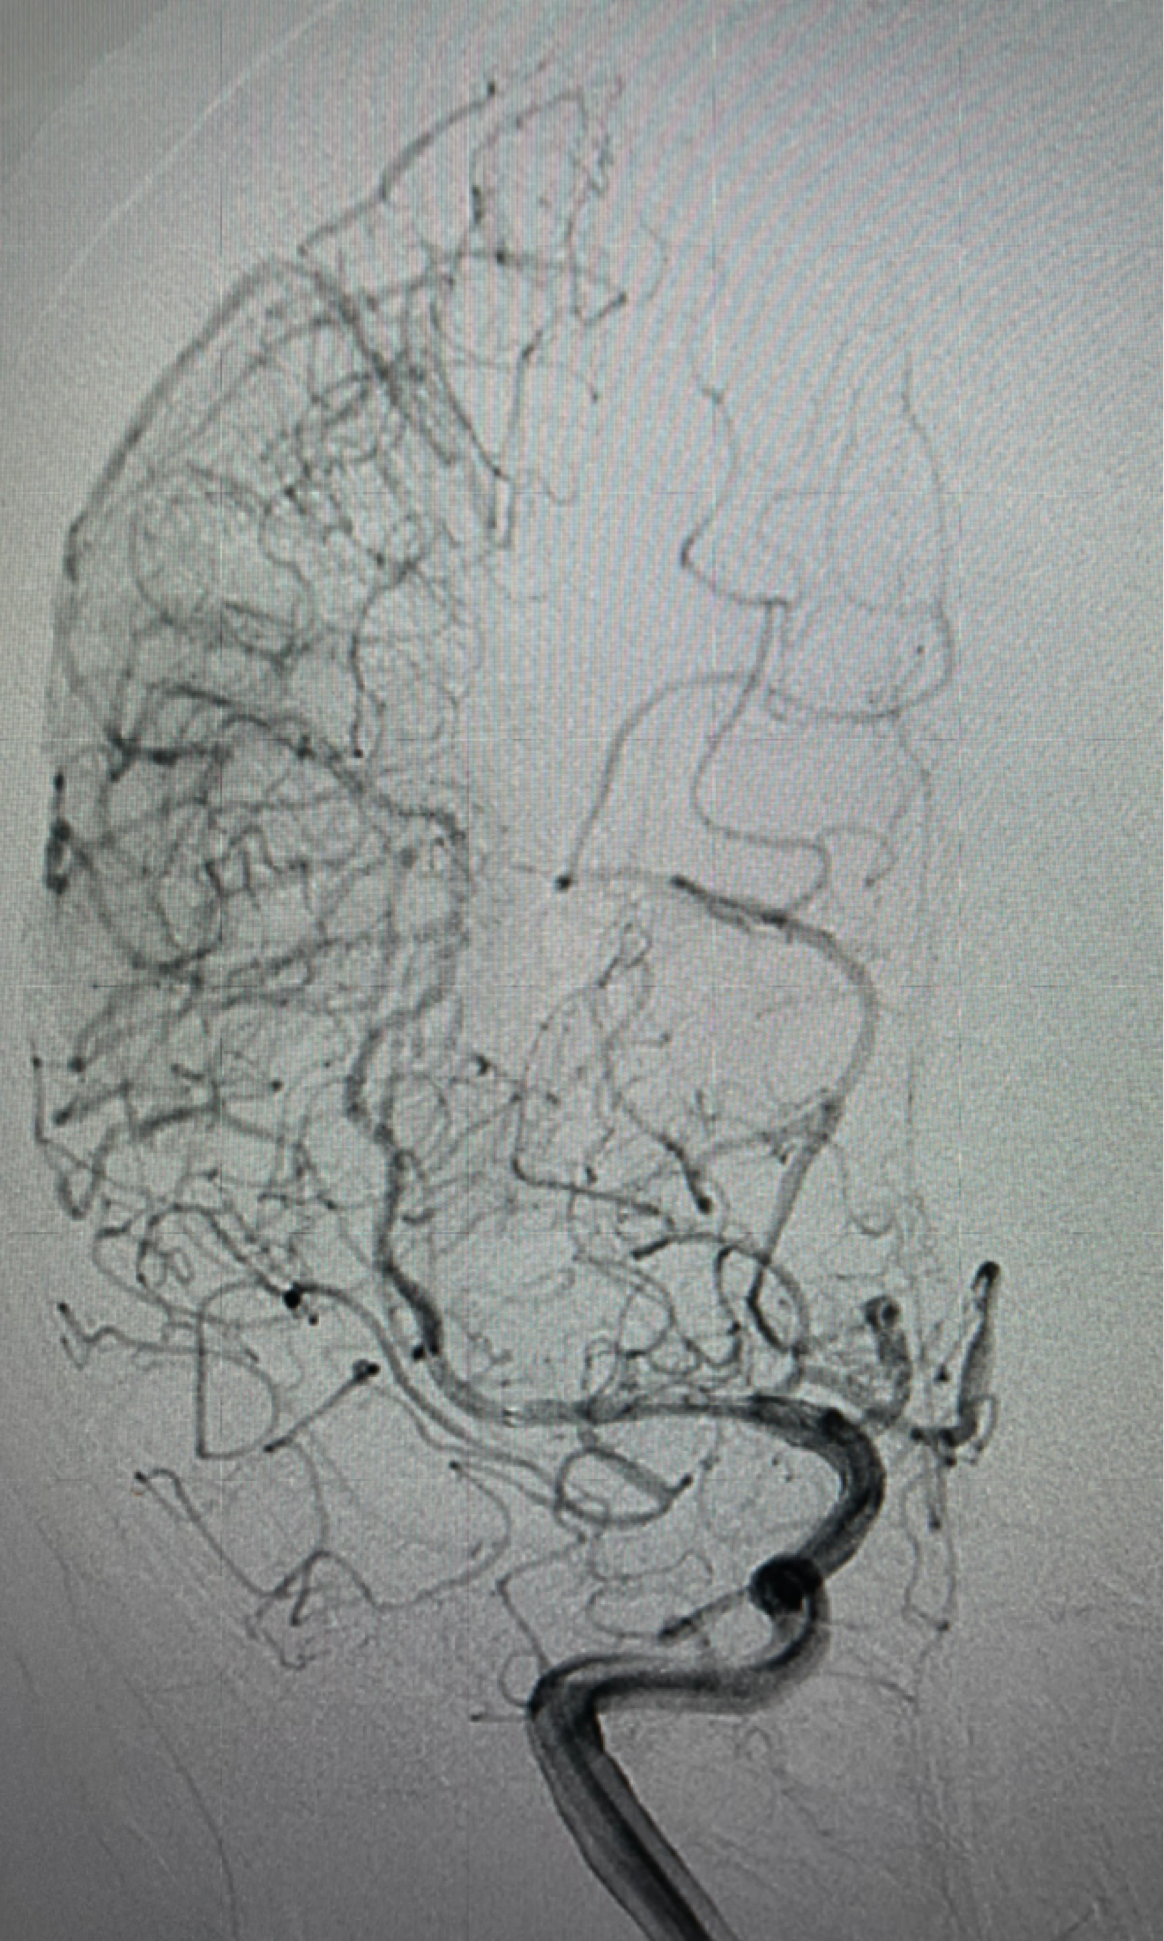

左侧颈内动脉正位造影提示前交通未开放

右侧颈内动脉造影提示大脑中动脉起始以远闭塞

颈内动脉侧位大脑前动脉A2以远闭全闭塞